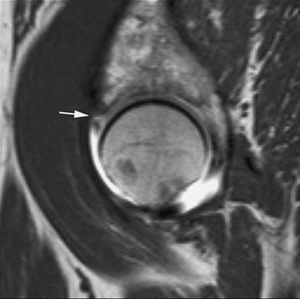

La RMA es una técnica con mayor eficacia diagnóstica en la valoración de las roturas meniscales recurrentes. Después de meniscectomías parciales, la capacidad de diagnosticar roturas recurrentes depende de la cantidad de menisco extirpado. Cuando la resección meniscal es menor del 25% los criterios de rotura en RM son los mismos que en la rodilla no operada --la fiabilidad de la RMA es similar a la de la RM en estos casos--. Cuando la resección es mayor del 75% la clínica del paciente no se asocia a las rerroturas meniscales. En los casos de resección entre el 25 y el 75% los criterios de rerrotura se basan en la introducción de contraste en el remanente meniscal (fig. 6)1,15,16.

Fig. 6.--Rerrotura de asta posterior del menisco interno. A, B) Corte coronal potenciado en T1 y corte sagital de RMA potenciado en T1 con técnica de supresión grasa en los que se observa introducción del contraste en el defecto meniscal.